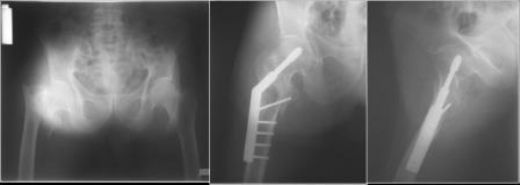

Kalça Kemiği Çatlağının Tanısı Kalça kemiği çatlağının tanısı, fizik muayene ve görüntüleme yöntemleri ile konulmaktadır. Fizik muayene sırasında doktor, ağrılı bölgeyi kontrol eder ve hareket kabiliyetini değerlendirir. Görüntüleme yöntemleri arasında:

Kalça Kemiği Çatlağının Tedavisi Kalça kemiği çatlağının tedavi yöntemi, çatlağın tipine ve ciddiyetine bağlı olarak değişiklik gösterir. Tedavi yöntemleri şunlardır: